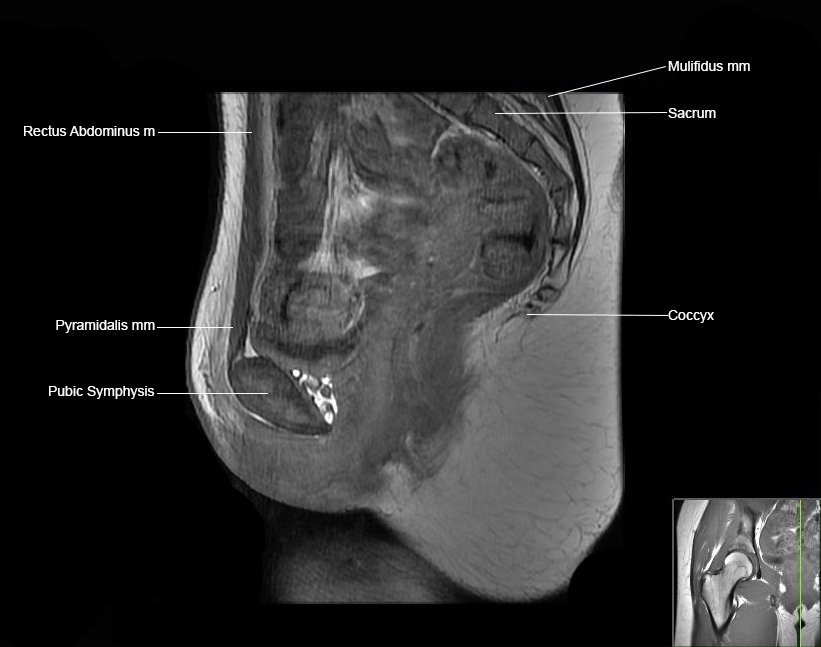

Hip

Basic Hip MRI

MRI Hip Anatomy

Scroll using the mouse wheel or the arrows